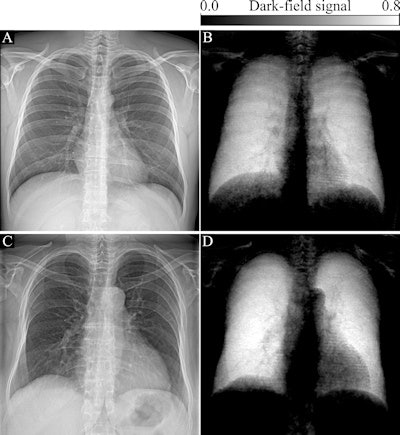

In attenuation-based radiography, dense structures generate a high signal, while in dark-field imaging, the small-angle scattering in lung tissue generates a high signal. Because dark-field x-ray imaging excludes unscattered photons, the space around the lungs appears dark (because there is no material there to scatter photons).

The researchers found normal human lungs on dark-field chest x-ray imaging produced high signal, while the surrounding osseous structures had low signal and soft tissue produced no signal. The average total dark-field signal intensity over all participants for the entire lung was (17 ± 4) × 10-3 m2 and the total signal demonstrated a positive correlation with lung volume (r = 0.61, p < 0.001).

"Because of the nature of signal generation in dark-field imaging, bone structures and soft tissue generate only a minimal dark-field signal compared with lung tissue. This feature allows for a detailed depiction of lung tissue without impairment by surrounding structures. We found that the quantitative x-ray dark-field coefficient based on the total dark-field signal and lung size is independent from the subject's characteristics," the researchers wrote.